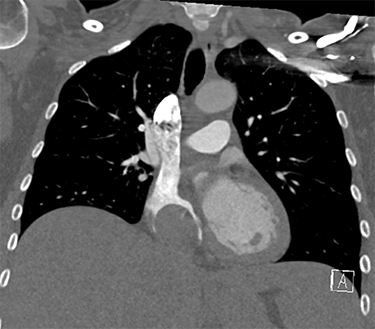

is the tumor growing out of Jessica's heart.

A scan found a 9-centimeter tumor thrombus, or fingerlike extension, growing from Jessica's inferior vena cava, the largest vein in the body that comes out of the back of the heart. The inferior vena cava brings blood from the lower body, pelvis and abdomen to the heart to be pumped into the lungs for oxygenation.